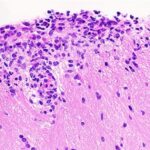

To assess Blimp-1 function in vivo during allergen or alarmin responses, we generated ILC2-specific, Blimp-1-deficient mice using the NMur1-Cre strain which includes eGFP as a marker of NMur1. NMur1 has been observed in non-ILC2 populations in other tissues but is restricted to the ILC2 compartment in the lung (Extended Data Fig. 5a,b). We administered IL-33 and IL-25 i.n. for 3 d and found ILC2 activation, including ST2 and KLRG1, and ILC2 numbers were not affected, indicating that Blimp-1 does not broadly regulate ILC2 activation or expansion (Extended Data Fig. 5c,d). However, Blimp-1 deficient ILC2s produced significantly more IFNγ and TNF compared to control ILC2s (Fig. 5a–d and Supplementary Fig. 3). Despite undetectable IFNγ protein in vitro, in vivo IFNγ was robustly increased which extended to bronchoalveolar lavage (BAL) (Fig. 5e). IL-5 and IL-13 were significantly reduced (Fig. 5f,g), suggesting that they may be indirectly regulated by increased type 1 cytokines. As early responders to tissue damage, ILC2s can influence the inflammatory state of T cell responses. We found increased expression of IFNγ and TNF in both CD4 and CD8 T cells in the lung (Extended Data Fig. 5e–j), although total numbers of both remained the same (Extended Data Fig. 5k,l). Decreased type 2 cytokines led to a reduction in eosinophil recruitment to BAL (Fig. 5h,i); however, mast cells were significantly increased, likely due to increased IL-3 and IL-9, because they can recruit mast cells (Fig. 5j,k)27,31. Neutrophils in the BAL were unaffected (Extended Data Fig. 5m). To assess the impacts on lung inflammation, we performed hematoxylin and eosin (H&E) and periodic acid–Schiff (PAS) staining to identify mucus in the airways. Blimp-1NMur1Cre mice had reduced lymphocytic infiltration and mucus in the airways compared to controlNMur1Cre mice (Fig. 5l–n). Collectively, these data indicate that Blimp-1 maintains the type 2 state of ILC2s, whereas its loss promotes a mixed phenotype expressing both type 1 and type 2 cytokines.

a,c, Representative flow plots of IFNγ+ (a) or TNF+ (c) ILC2s in indicated mice after IL-33 + IL-25. b,d, Quantification of IFNγ (b) or TNF (d) from a and c (n = 6). e, Quantification of IFNγ in BAL by ELISA (n = 3). f, Representative flow plots of IL-5+ IL-13+ ILC2s in indicated mice after IL-33 + IL-25. g, Quantification of IL-5 (left) or IL-13 (right) expression from f (n = 6). h,j, Representative flow plot for eosinophils (h) or mast cells (j) in indicated mice after IL-33 + IL-25. i,k, Quantification of eosinophil number (i) or mast cell numbers (k) from h and j (n = 3). l, Representative H&E and PAS staining of lungs from the indicated mice after IL-33 and IL-25 i.n. m,n, Quantification of inflammation (m) and mucus (n) from l (n = 4) Each point represents one individual sample. The data are shown as mean ± s.d. and represent two independent experiments. A two-tailed, unpaired Student’s t-test was performed for b, d, e, g, i, k and n and Šídák’s multiple-comparison test for m. *P < 0.05, **P < 0.01, ***P < 0.001, ****P < 0.0001. The specific P values are as follows for b: P = 0.0021; for d: P = 0.0007; for e, P = 0.0112; for g: left, P < 0.0001, right, P = 0.0009; for i: P = 0.0326; for k, P = 0.0029; for m, normal, P = 0.0428, inflamed, P = 0.0223, bronchi, P = 0.9867; and, for n, P = 0.0095. NS, not significant; ROI, region of interest.